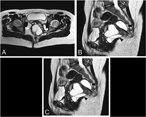

Wide rectal duplication cyst in an adult resected by anterior approach: efficacy and recurrence

Michela Ceriotti and others

Journal of Surgical Case Reports, Volume 2017, Issue 6, June 2017, rjx115, https://doi.org/10.1093/jscr/rjx115